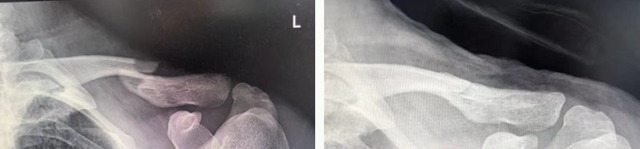

左:复位前 右:复位后

另外2名少年锁骨骨折轻度移位,病情相对缓和,团队同样采用“手法复位+8字绷带固定”的经典中医方案,快速完成复位固定后,同样施以中药外敷调理,有效缓解疼痛肿胀,促进骨折愈合。

小林的锁骨骨折最为严重,为粉碎性,若行开放手术,不仅手术切口大,出血多,钢板内固定后还可能影响骨骼后续生长。传统中医手法正骨具有不开刀、不出血、不留疤、费用低等特点。医生运用“推端提按、抱迫靠拢”等正骨手法,蓄力指尖,擒拿扶正,将分散的骨折碎片精准拼接、复位;再用杉树皮小夹板固定,既牢牢锁住骨折端避免再次移位,又不压迫局部皮肤导致皮肤溃疡;同时辅以医院自制的消肿止痛中药外敷,辅以活血化瘀内服方剂,促进骨痂生长和创伤修复。